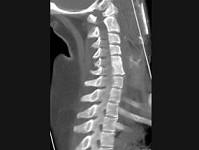

问题 男,35岁,反复颈部不适20余年,结合图像,最可能的诊断是?(?)

选项 A.颈椎椎体融合 B.颈椎结核 C.颈椎退行性变 D.颈椎压缩性骨折 E.颈椎骨转移瘤

答案 A